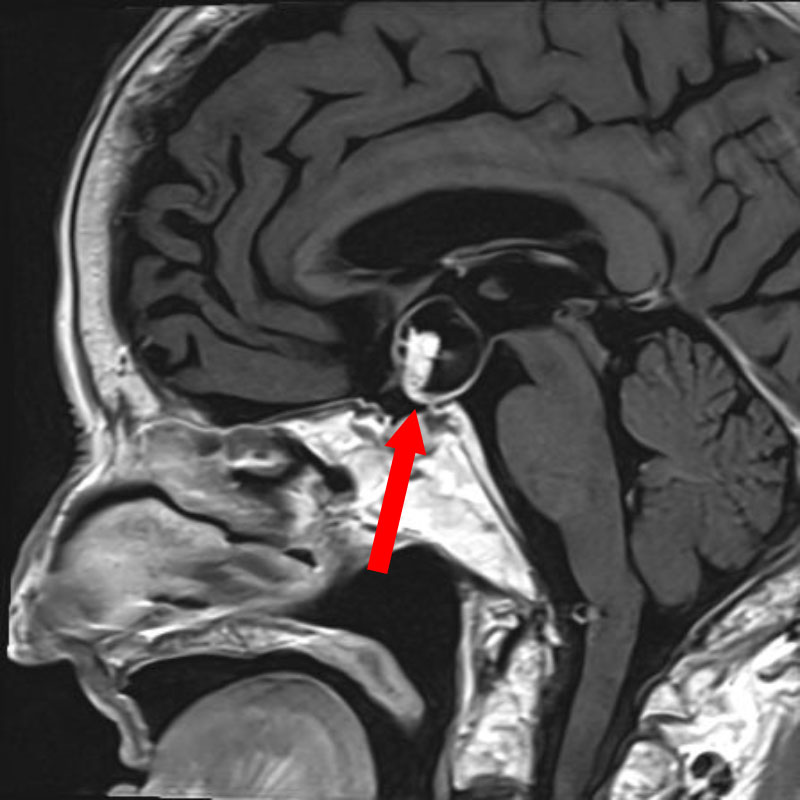

断層撮影

手術前1

手術前2